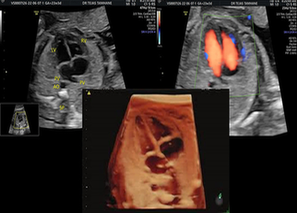

A fetal echocardiography is a specialised ultrasound focused solely on the baby’s heart. Unlike a routine anomaly scan, it provides a detailed assessment of cardiac structure, blood flow, rhythm and function. When done by an experienced Fetal Medicine Specialist, it can identify even subtle cardiac abnormalities long before delivery.

Fetal cardiac anomalies range from minor defects that may resolve on their own to complex structural heart diseases requiring immediate intervention after birth. Conditions like ventricular septal defects, hypoplastic heart syndromes, transposition of great arteries and valvular abnormalities usually develop early in gestation. The challenge here is that many of these conditions are not easily detected on standard ultrasound scans, especially in high-risk pregnancies where multiple factors can complicate imaging.

Fetal echocardiography is usually done between 20 and 24 weeks of gestation, when the fetal heart is developed enough to allow accurate evaluation. In certain high-risk cases, earlier scans may be advised, followed by repeat assessments later in pregnancy. Timely diagnosis helps in close monitoring and, in select cases, in-utero interventions.